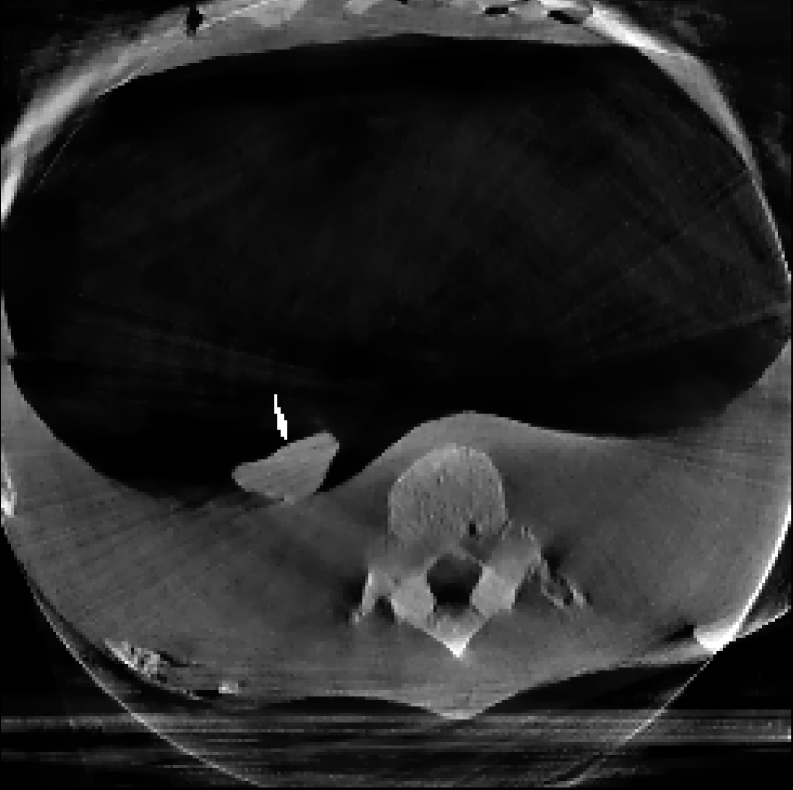

In this example, we reconstruct a Thorax phantom scanned using the Phillips Allura FD20 Xper C-arm CBCT scanner. This device has source-to-axis and source-to-detector distances of 810 mm and 1195 mm respectively, and an installed detector of size 30×\times40 cm2 with 0.776 mm pixel pitch. Moreover, the data has a resolution of 364×512×364\times 512\timesnumber of projections and the image is reconstructed with a resolution of 256×256×256256\times 256\times 256 voxels.

The reconstructions corresponding to the real-scan data with different number of projections (180, 50, and 20, respectively), can be observed in Figures 3, 4, and 5. In all three figures (a) is the prior image 𝒙p\boldsymbol{x}_{p} used for prior image regularization, (f) is the ground truth image; and the rest of images correspond to different reconstructions (top) with their corresponding errors (bottom). Analogously to the previous experiment, the difference images (or error) should be completely black in the case of a perfect reconstruction and high intensity indicates more inaccurate reconstructions.

Note that the real data contains a lot of measurement noise, and due to the presence of the needle, the reconstructions can suffer from strong metal artifacts. Therefore, the reconstructed images using different algorithms, particularly without explicit regularization, tend to show strong errors even with a high number of projections. Accordingly, all the algorithms with explicit regularization perform better in this scenario, and particularly those including PIPLE or PICCS regularization. Moreover, the proposed IRN-PIPLE algorithm significantly outperforms other methods, and IRN-PICCS is not far behind. Using only TV regularization struggles to separate artifacts from features, oversmoothing images and thus loosing important image features. Notably, the proposed methods reconstruct high quality images in less than 2 minutes in an implementation that is not optimized to solve this specific geometry.

Figure 3: Reconstructed images using real measurements of a thorax phantom with 180 projection. The reconstructed images are shown in [0, 0.03]; difference images in [–0.04, 0.04].